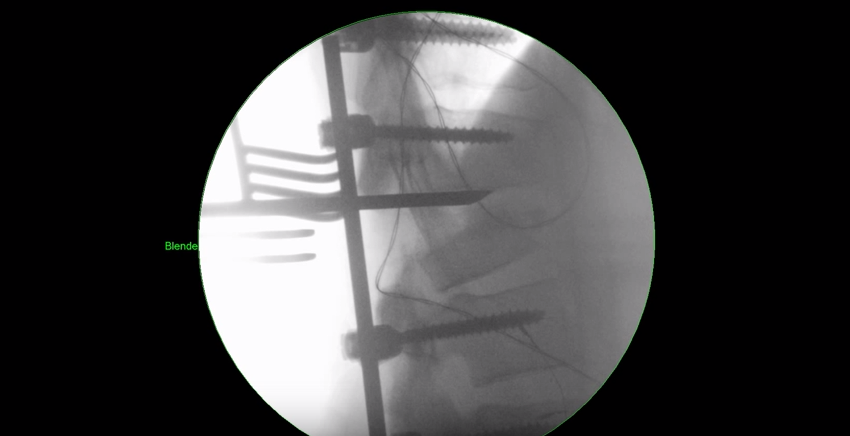

Wenn wir älter werden, nehmen die Verschleisserkrankungen zu. Und die Wirbelsäule verliert oft die gerade, aufrechte Struktur und wird krumm und krümmer. Im Röntgenbild sehen wir oft ganz verschiedene Verschleisssituationen nebeneinander. Da die Wirbelsäule aus verschiedenen Bewegungssegmenten besteht, muss der Wirbelsäulenchirurg genau wissen, woher der Schmerz kommt. Würde man sich…